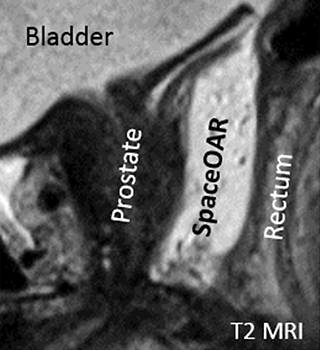

SpaceOAR®システムのMRI画像

矢状断面

放射線の影響は距離が離れれば低減します。そのため、当院では前立腺と直腸の間にゲル状の物質を挿入し、前立腺と直腸の間を1.0~1.5cm離すことで直腸被曝を低減させる処置として、『直腸周囲ハイドロゲルスペーサ・SpaceOAR®』の留置を行っています。

ハイドロゲルは注入後、前立腺と直腸の間に約3カ月間スペースを維持し、その後約6カ月かけて体内に吸収されます。